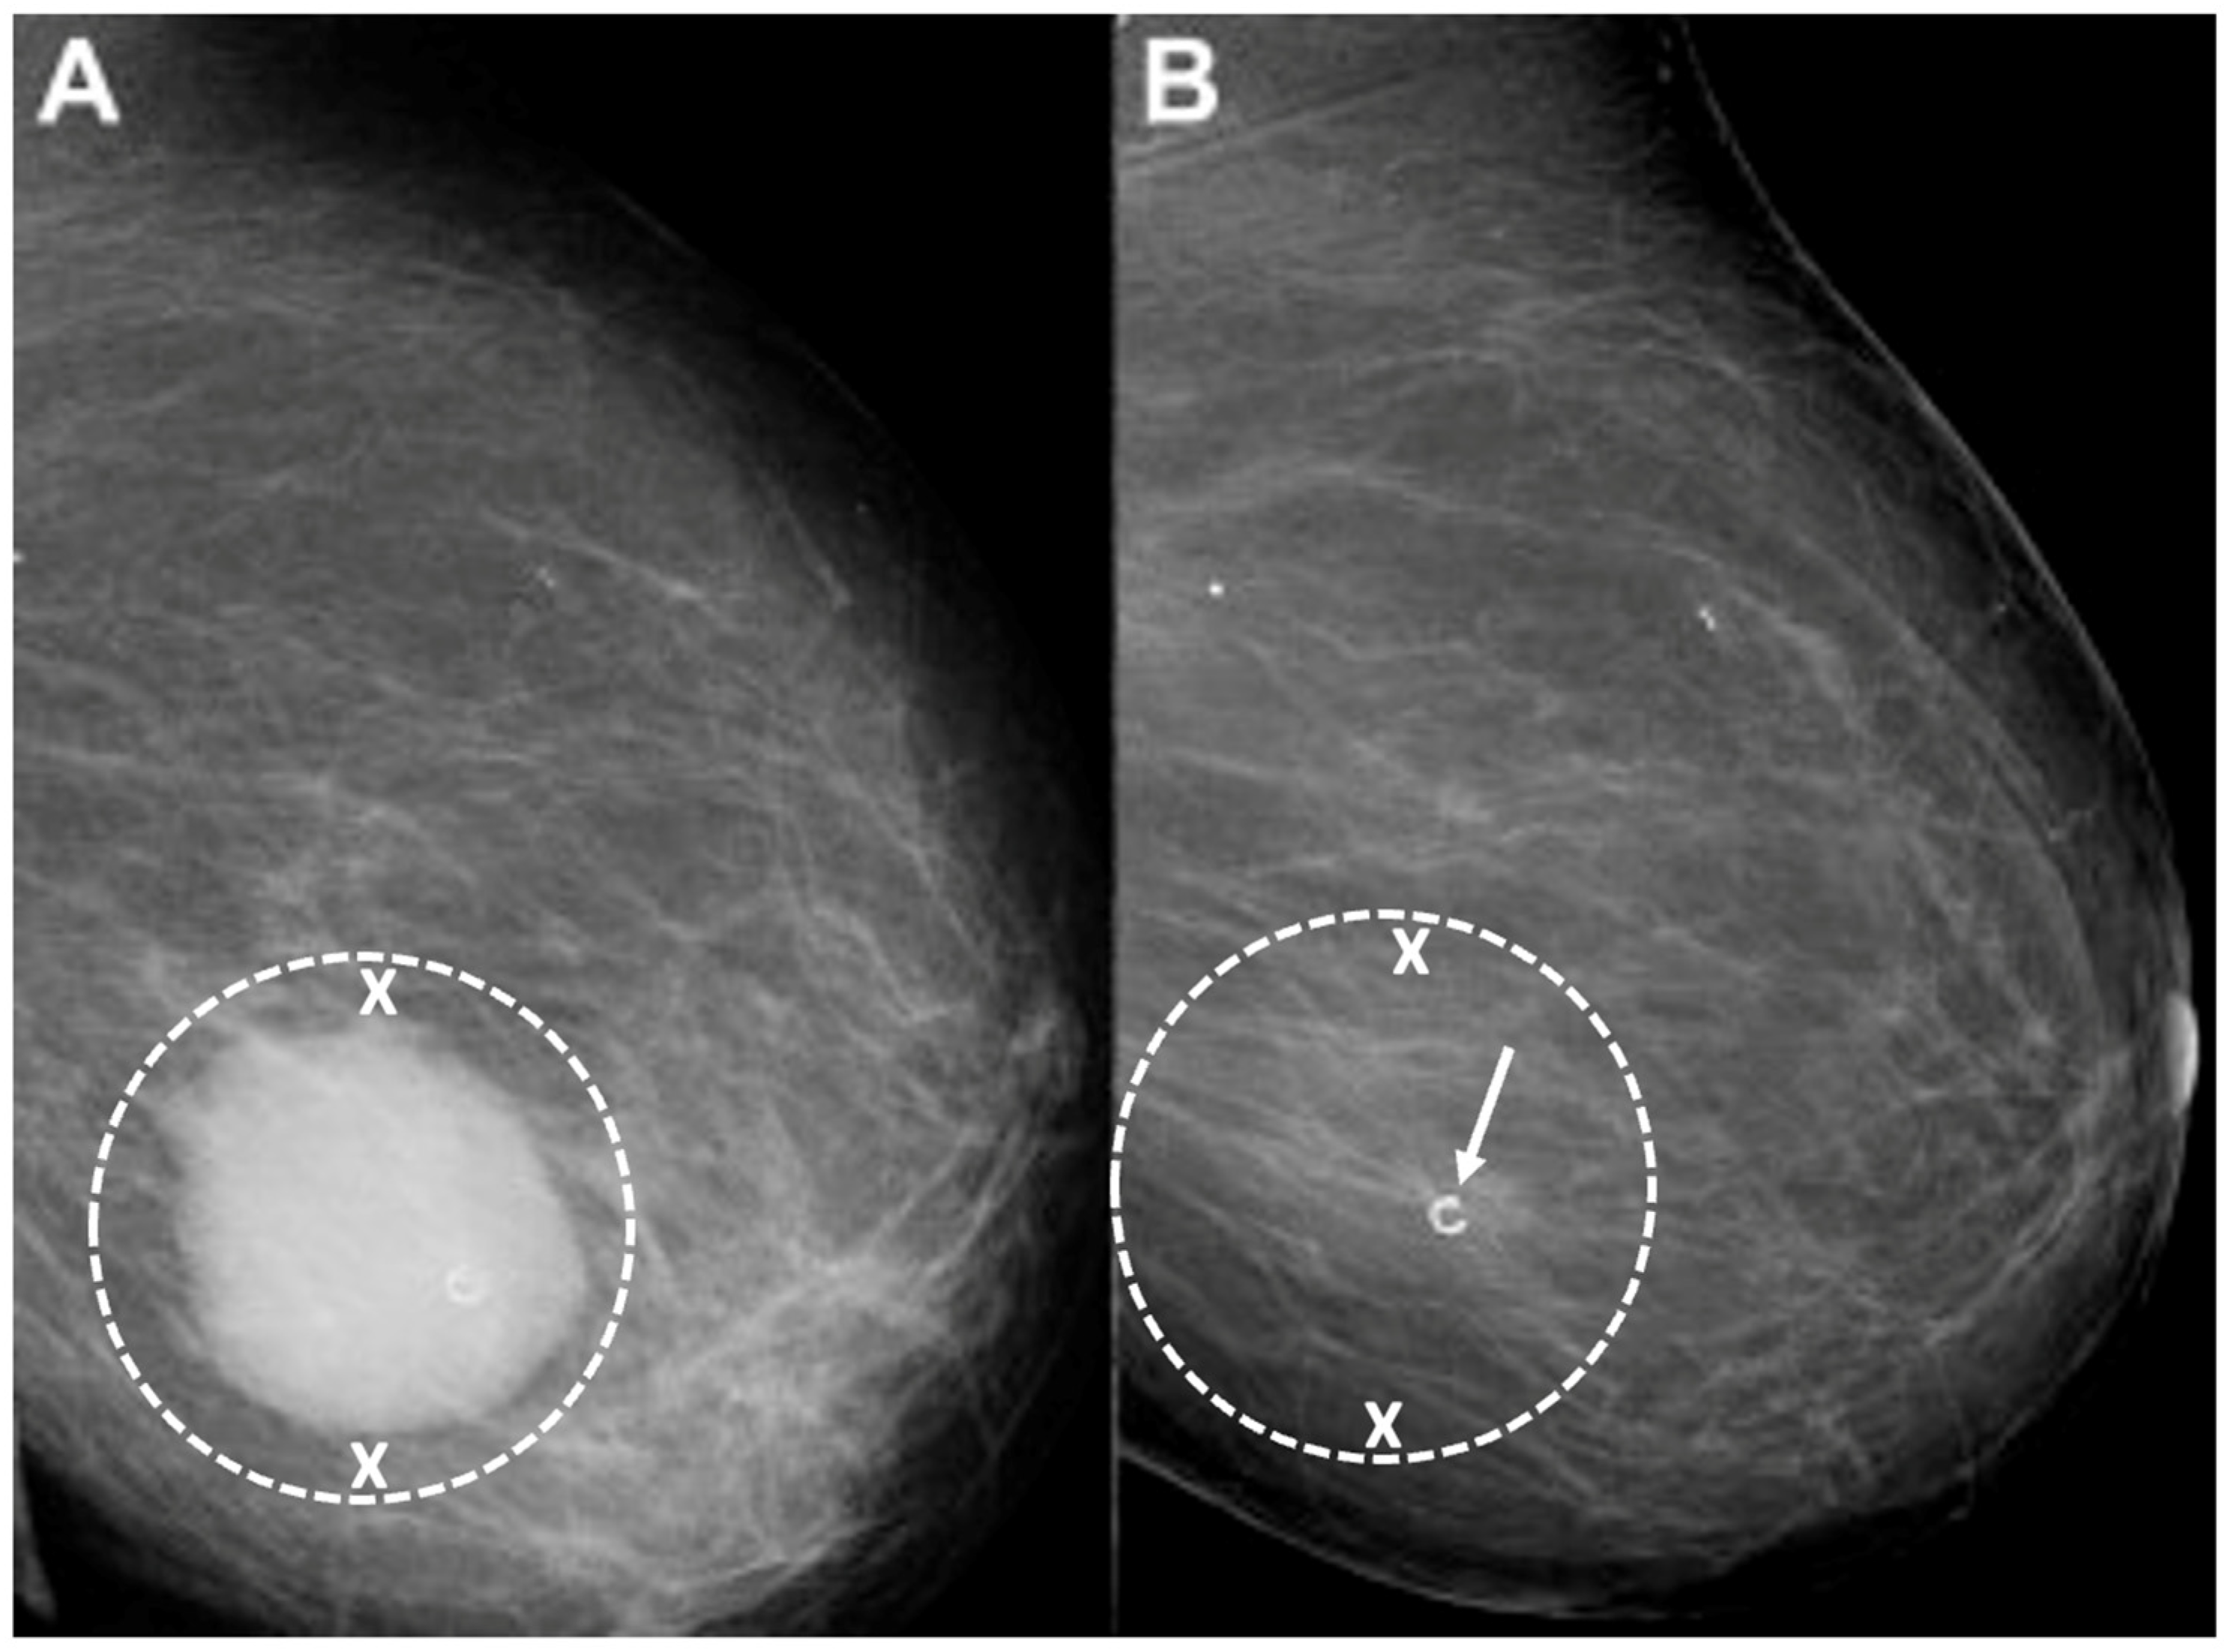

Placement of biopsy site marker(s). Regardless of cancer size, insertion of a biopsy site marker (also called a “clip” or “chip”) at the time of mammogram-, ultrasound-, or MRI-guided needle biopsy is recommended to document the site of the cancer. In situations where pre-cryoablation chemotherapy and/or anti-HER2/neu therapy is planned, insertion of a biopsy site marker prior to initiation of anticancer medications documents the location of the cancer in the event drug therapy-induced shrinkage of the cancer makes it difficult to detect by ultrasound (Figure 5).

Figure 5.

Mammogram performed before (A) pre-operative chemotherapy showing large, white, ultrasound visible cancer encircled by hash marks. After completing pre-operative chemotherapy, a repeat mammogram (B) of the same breast showed complete disappearance of the original cancer leaving only a circular metal biopsy site marker (arrow) to indicate the location of the original cancer.

- Target cryoablation of the original tumor volume. Although neoadjuvant systemic therapy might induce the complete radiographic disappearance of the cancer, individual cancer cells or microscopic clusters of cancer cells could persist throughout the span of the original cancer (Figure 19). Therefore, targeting the original tumor volume plus a surrounding ablation margin has a greater potential to achieve complete ablation at the cancer site. This strategy contrasts with how patients are managed surgically after neoadjuvant systemic therapy, where the ability to perform microscopic examination of the surgical margins permits the initial excision of a smaller volume of tissue followed later by margin re-excision if the microscopic assessment reveals residual cancer at the surgical margin.

Figure 19. Mammograms performed before (A) and after (B) chemotherapy showing representative locations (indicated by “X” marks) where bracketing biopsy site markers can be placed before starting chemotherapy to mark the edges of the white, dominant cancer dimensions in the event the mass is no longer visible after chemotherapy. Figure B shows the same breast after completing chemotherapy showing complete resolution of the mass and the representative locations of bracketing site markers (indicated by “X” marks) placed before chemotherapy to outline the original tumor dimensions.